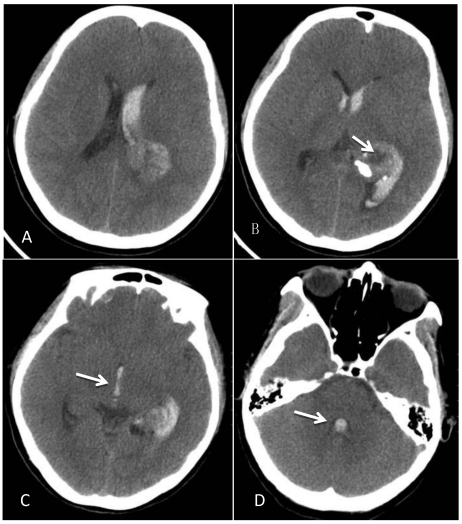

Figure 1.

CT at the time of onset of intraventricular hemorrhage. A-B: A space-occupying lesion in the trigone of the left lateral ventricle was observed; it had a low-density cystic shadow in the middle (arrow). A high-density calcification shadow was detected at the rear of the lesion, and the surrounding brain tissues were mildly compressed. C: Hemorrhage surrounded the lesion and formed a hematoma, which extended forward into the lateral ventricle, and the hemorrhage affected the third ventricle (arrow). D: The hemorrhage also affected the fourth ventricle (arrow).